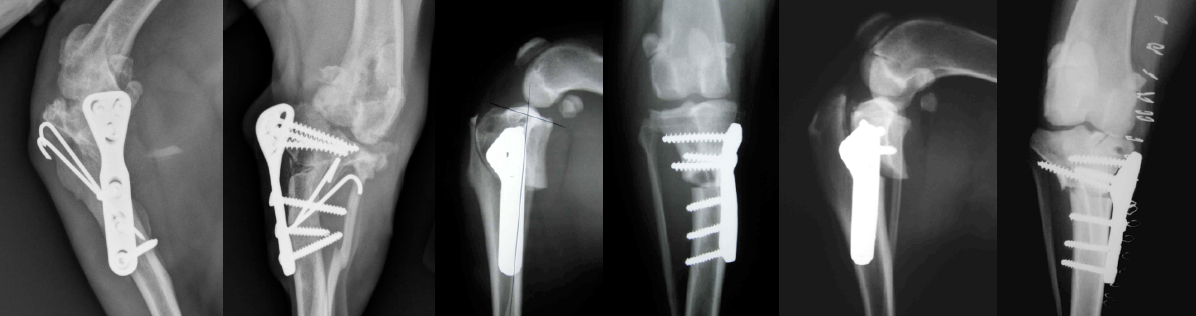

The immediate postoperative radiographic images at the right are examples of precise TPLO planning, excellent limb alignment and ideal orthopedic implants size and position.

Below are four cases of previously operated dogs referred to ACOSM for salvage. Each is an example of poor TPLO techniques and outcomes. In the case of the second series of radiographs, serious intra-operative complications associated with TPLO, a broken jig pin, poor surgical technique and resulting formation of a ring sequestrum resulted in uncontrolled infection and loss of the limb.